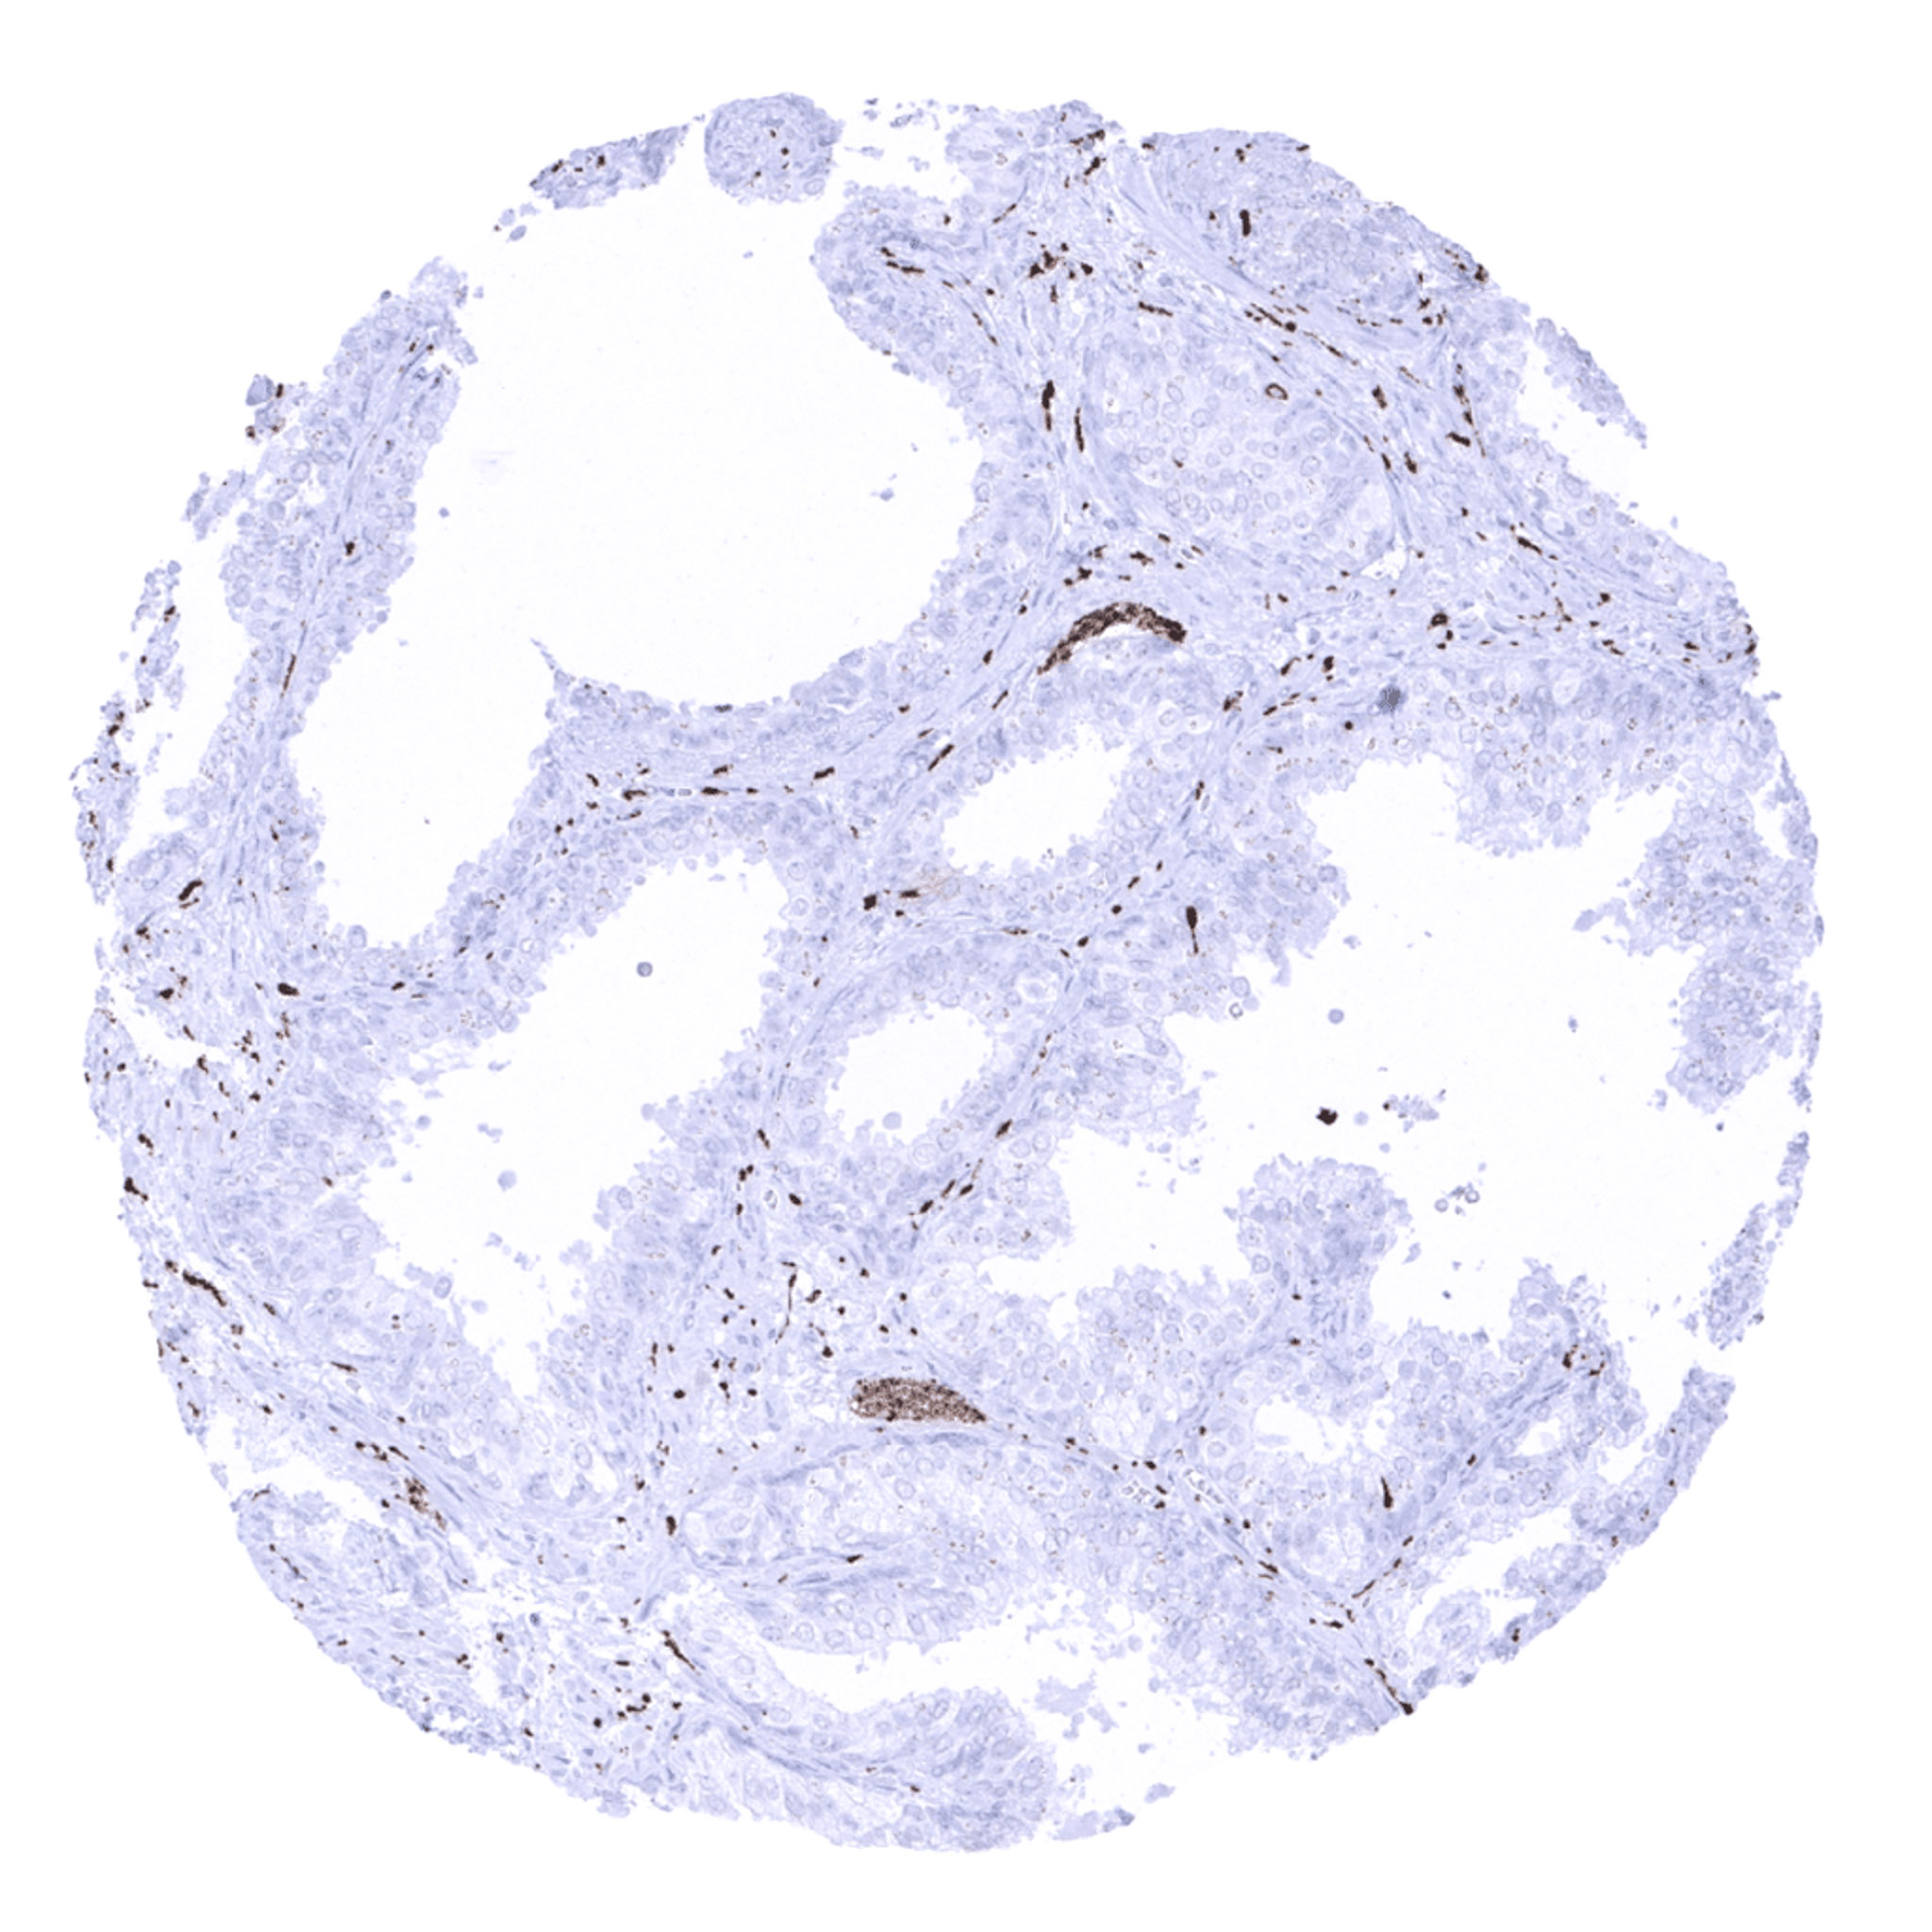

Prostate